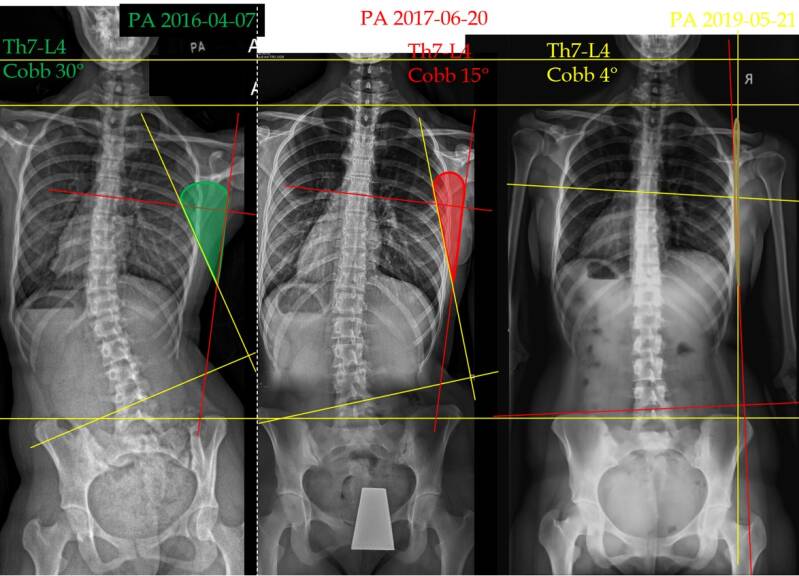

• Scoliosis

We are checking the treatment outcomes utilizing photo documentation and control images – X-ray, MRI, and CT, where available.